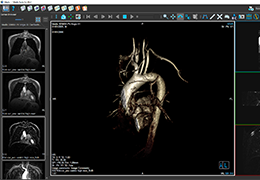

ANYTHINK 经导管主动脉瓣膜置换术分析系统

| 销售价格: | ¥ N/A |

| 商品编号: | AS-CAD-326-0961 |

| 软件语言: | 中文/英文 |

| 器械分类: | II |

| 生产厂家: | 北京思创贯宇科技开发有限公司 |

| 公司网址: | http://www.crealifemed.com/ |

| 认证信息: | CFDA |

| 系统要求: | Windows |

| 交付方式: | 下载安装 |